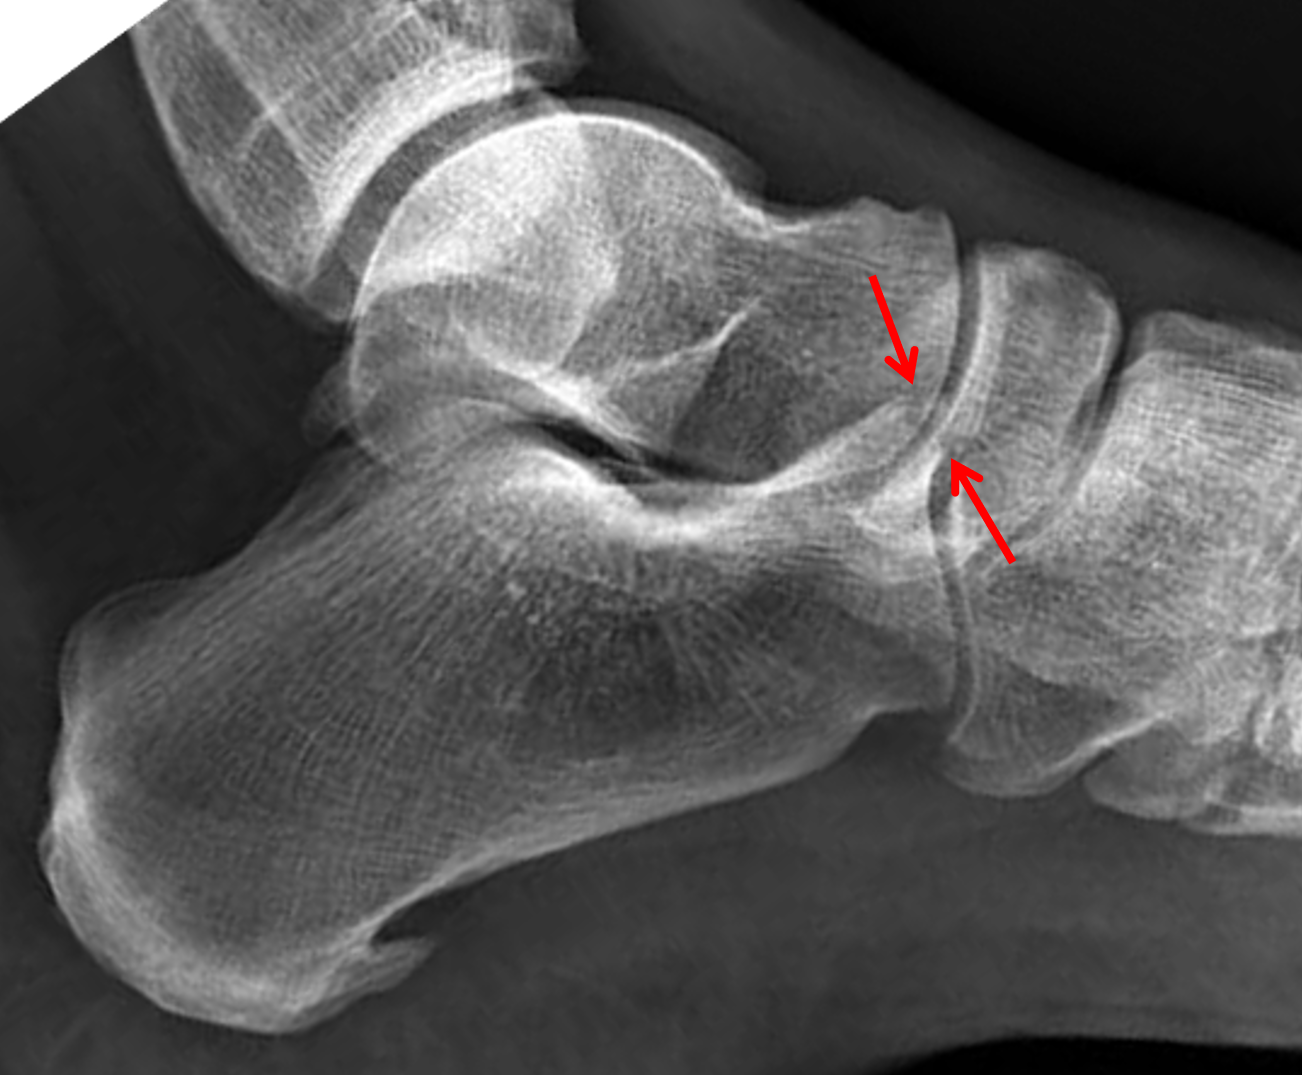

Anterior process articulates with cuboid and navicular. Anterior process of the calcaneus. It is a rare type of fracture but has potentially debilitating results. Answer | the anterior process of the calcaneus usually fractures due to an avulsion or traction injury. The precise location of a trigger point aids in the diagnosis, which must be confirmed by careful roentgenographic observations. Subtle clinical presentation and the anterior portion of the calcaneus body is a distinct, well recognized and clinically important part of this bone; fractures of the anterior process of the calcaneus. Sclerotic line may be only evidence of impacted fracture. Fracture of the anterior process of the calcaneus is a common injury that is often misdiagnosed. The number of reported cases of fractures of the anterior processus of the calcaneus is small and the true incidence cannot be determined because the diagnosis is often missed. A calcaneal fracture is a break of the calcaneus (heel bone). It usually occurs when a person lands on their feet following a fall from a height or during a motor. Minimally displaced but slightly comminuted fracture of the anterior process calcaneus (arrows) with considerable overlying soft tissue swelling involving the subcutaneous tissues and bifurcate ligament. The bifurcate ligament pulls on the anterior aspect of the calcaneum resulting in a fragment of bone being pulled away. Comorbidities that preclude good surgical outcome (smoker, diabetes, pvd). The key to management of this injury is an accurate diagnosis and proper treatment. Inversion with plantar flexion can lead to an avulsion fracture.